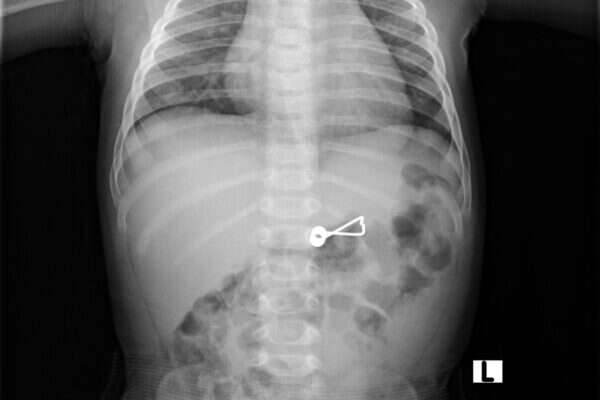

תינוק בן חצי שנה, מאחד מיישובי עמק יזרעאל, הובהל לבית החולים העמק בעפולה, לאחר שבלע קפיץ של אטב לתליית כביסה. אמו סיפרה לצוות הרפואי בחדר המיון כי בעת שהיתה עסוקה בתליית כביסה נשבר אחד האטבים והפעוט, שהיה בסמוך אליה, התנפל על המציאה והכניסה מיד לפיו. תחילה הראה התינוק סימנים של מצוקה נשימתית והוריו חששו שהאטב חוסם את דרכי הנשימה שלו. אולם בבדיקות הדמייה שנערכו לתינוק עם הגיעו למחלקה לרפואה דחופה, התברר כי למרבה המזל, התינוק הצליח לבלוע את הקפיץ והוא ממוקם בקיבה.

"מידי שבוע אני שולף גופים זרים מהריאות ומדרכי הנשימה של פעוטות בגיל שבו הם מכניסים לפה כל דבר שבדרכם, אבל עדיין לא נתקלתי בקפיץ גדול שפעוט הצליח לבלוע מבלי שהוא נתקע בוושט או בריאה. למרבה המזל הקפיץ הגיע לקיבה אולם גם שם יכול היה להיגרם נזק חמור משום שהקפיץ עלול לגרום לנקב בקיבה או במעי הדק שזהו מצב מסכן חיים", סיפר ד"ר עזמי שחברי, מומחה בכיר לגסטרואנטרולוגיה במרכז רפואי העמק.

צילום: דוברות ביה"ח העמק

לדברי ד"ר שחברי, "לאחר שהצילום בסי.טי הדגים את מיקומו המדוייק של הקפיץ, הוחלט שיש להוציאו בפעולה כירורגית בחדר הניתוח. הפעוט הורדם, והוצאתי את הקפיץ מקיבתו בפעולת גסטרוסקופיה, באמצעות מכשור משוכלל שבקצהו מצלמה ובאמצעותו ניתן לשלוף את הגוף הזר". לאחר הניתוח הועבר התינוק להתאוששות ומשם לאשפוז והשגחה במחלקה לכירורגיית ילדים.